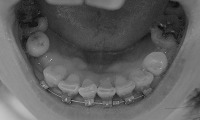

30代後半より、歯列矯正始めました。

不可思議な現象に悩まされながらも、

なんとかがんばってます~。